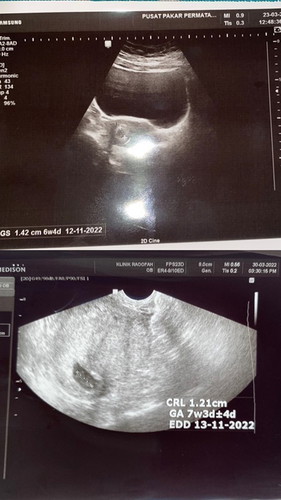

Baca lagiTerima kasih 😢🤲🏻🤍 haah takde heartbeat. Mula mula scan apa pun takde. Doctor cakap kandungan luar rahim. Second scan, kantung je yg ada. Third scan kantung janin tapi heartbeat tak ada. Tak apa lah. Bukan rezeki saya nak dapat first pregnancy baby lahir. Terima kasih ya sis banyak bagi kata semangat ❤️❤️❤️❤️